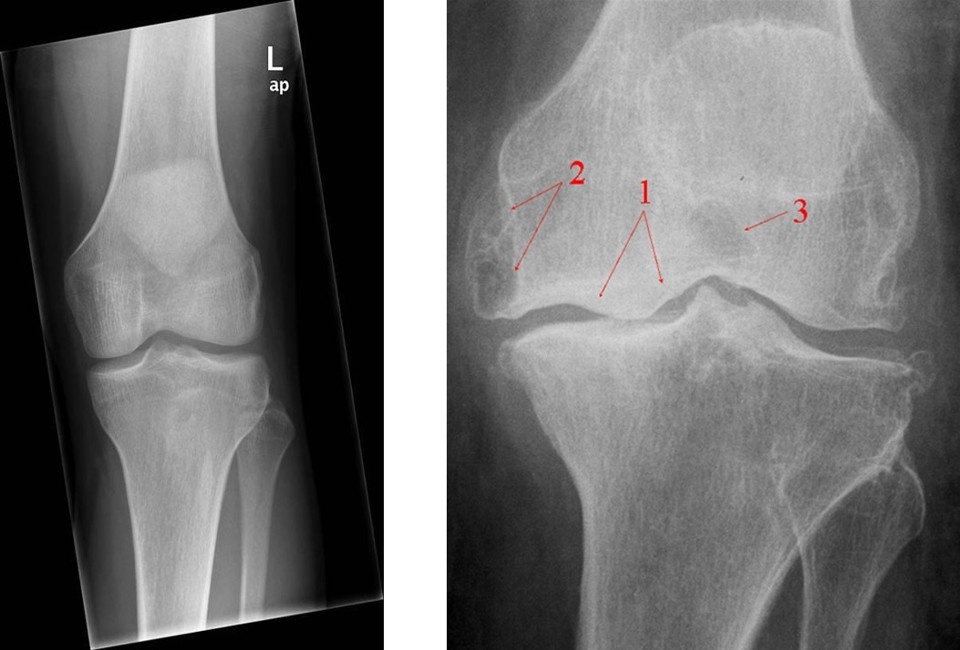

Den opdaterede beskrivelse indeholder klare retningslinjer for, hvornår henvisning til træning, røntgenundersøgelser og ortopædkirurgisk afdeling er relevant.

Et flowchart illustrerer de relevante trin i processen fra almen praksis til evt. operation.